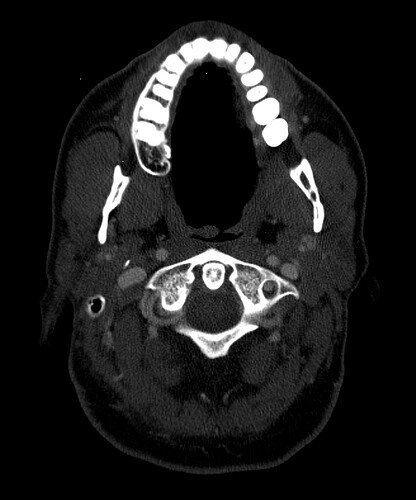

I did have an MRA done at Mayo that showed severe blood flow compression on my left side with my arms up. Because of this test, I went back to UCLA and did tests for Thoracic Outlet Syndrome. The limited tests they can do for this seemed to help. So, I had a left rib resection 2 yrs ago. Before this surgery, I did do a CT w/wo contract to look for Eagles and the report came back saying my stylohyoid was normal. So I went ahead with the thoracic outlet surgery. That surgery got rid of the daily headache I was dealing with. It seemed to have relieved pressure headaches and some of the loss of feeling in my arm. It never helped with the facial pains and dizziness though that I live with. Months after this surgery, I also developed Frozen Shoulder. I found it odd I got this so long after the surgery and when I was in PT. It seemed like the more we tried to use my arm and mess with my neck, the worse it got. I then went back to Mayo and had a head and face MRI that showed compression of my vagus nerve with an artery around my brainstem. It also showed a blood vessel touching my trigeminal nerve which is what they look for with trigeminal neuralgia surgery. So I took this and followed this lead. After visiting three trigeminal neuralgia surgeons, most of them said since I didn’t live with shooting lightning pains, I wasn’t a good candidate for the surgery. I was referred to some neurosurgeons regarding the vagus nerve compression at the brain stem. I almost had surgery booked for this and then the dr said something more is going on here, let’s hold off. This led me to circle back to Eagles Syndrome. Even though my CT hadn’t shown eagles on the report, I took it to Dr. Osborne. He indicated I had a calcified ligament. I almost moved forward with surgery, but I am concerned about the vascular issues I know I’m experiencing. I worry that I need to ensure we target these issues in my surgery. In the past few years, I’ve had near fainting spells, dizziness (I no longer can drive), BP issues that were similar to POTS but not, heart palpitations, horrible brain fog, and a complete inability to concentrate. I also get left sided body numbness and weakness. My left leg can even be impacted. It’s not to where I can’t walk but it feels like I’m living on a cruise ship trying to balance myself and my left side is weak. I feel like I need to confirm I have vascular issues and make sure I care for this in surgery. I tried to get a second opinion with an ENT at UCLA and they said they saw nothing wrong with my stylohyoid but that they see something wrong with my hyoid bone that they might be willing to operate on.

I really need help reading my images myself. I have anonymized them, but I don’t even know how to provide the right image to view here. I want to be able to advocate well for myself but I need to know what I’m looking at. I feel like the group on here know more than any doctors at this point. I would love to get back to normalcy…driving my kids around, actually getting sleep, being able to think clearly, being able to physically exercise, to be thriving and not barely surviving. Things I took for granted before this, I won’t again. Pls help if you are able. I can post my images following this first post though guidance on steps would be appreciated.